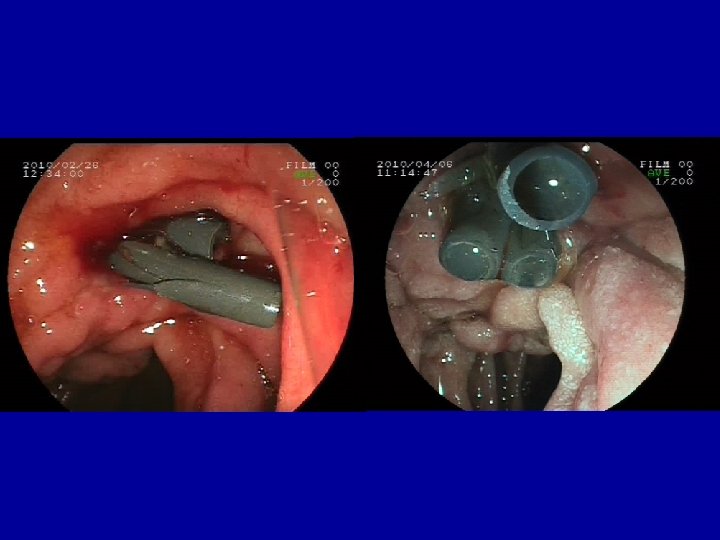

Case report VIII. • 2010 Febr. ERCP: Pancreas divisum with unequivocal changes in the ventral ducts. • Patulous secondary papilla with suprapapillary restenosis and distal dilatation of dorsal duct, • Dilation, 10 F pancreatic stent + 5 F nasopancreatic catheter with citrate lavage for 3 days followed by another 10 F stent placement into the dorsal duct

Case report IX. • 2010 Apr. another 10 F pancreatic stent to calibrate stenosis equilibrating prestenotic dilatation (10 mm=3 x 10 F), • no pain at dilation and further on. • Planned removal after 6 month

Multiple biliary and pancreatic stents with guidewire in the papilla

Biliary and pancreatic stents in the corresponding ducts Pancreatic lavage with citrate (1. 9%) at 1 -2 ml/min for 3 -5 days